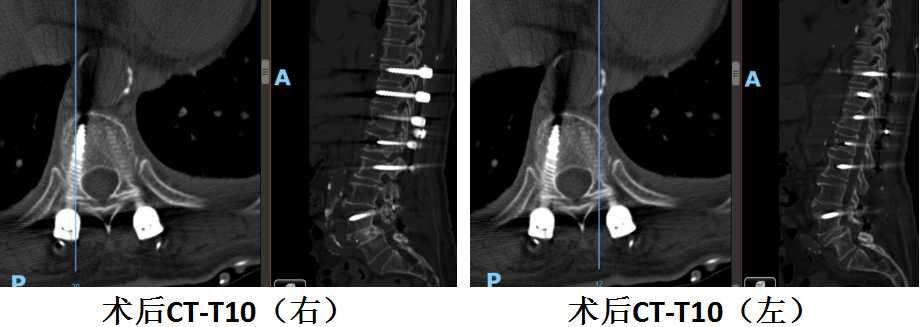

陈奶奶术后胸10水平螺钉位置良好